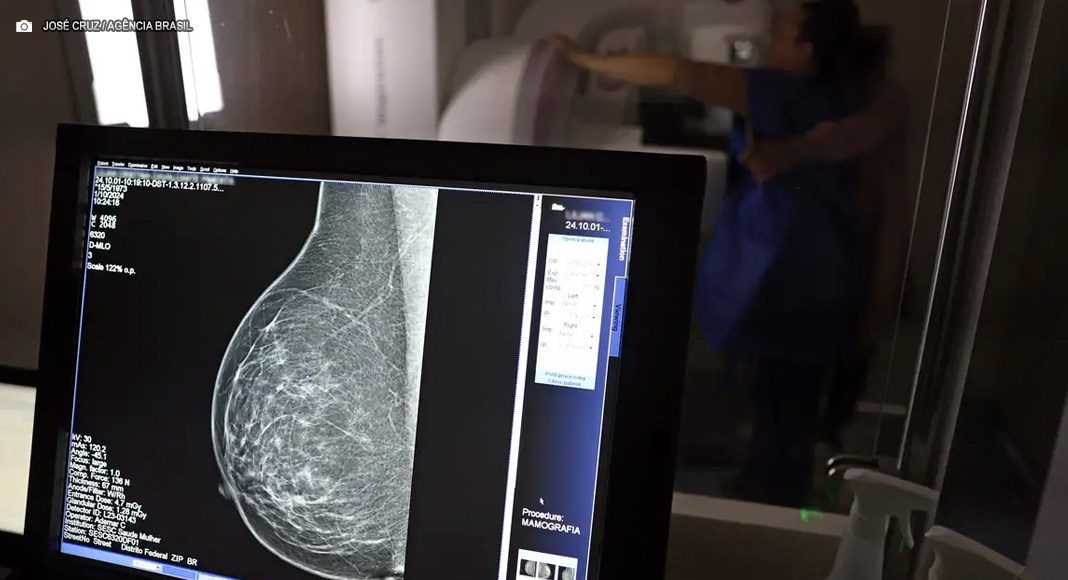

Para a entidade, os números reforçam a importância de ampliar o rastreamento do câncer de mama por meio da realização de mamografia em mulheres abaixo dos 50 anos e acima dos 70 anos, faixas etárias que não estão incluídas na recomendação padrão de exames preventivos no âmbito do Sistema Único de Saúde (SUS).

O levantamento mostra que, entre janeiro de 2018 e dezembro de 2023, o Brasil registrou mais de 319 mil diagnósticos de câncer de mama, sendo 157,4 mil em mulheres de 50 a 69 anos, faixa etária atualmente recomendada para o rastreamento.

Entre mulheres com idade entre 40 e 49 anos, foram registrados 71.204 casos de câncer de mama, enquanto 19.576 mulheres com idade entre 35 e 39 anos também receberam o diagnóstico da doença. Juntas, ambas as ocorrências representam 33% do total de casos diagnosticados no período.